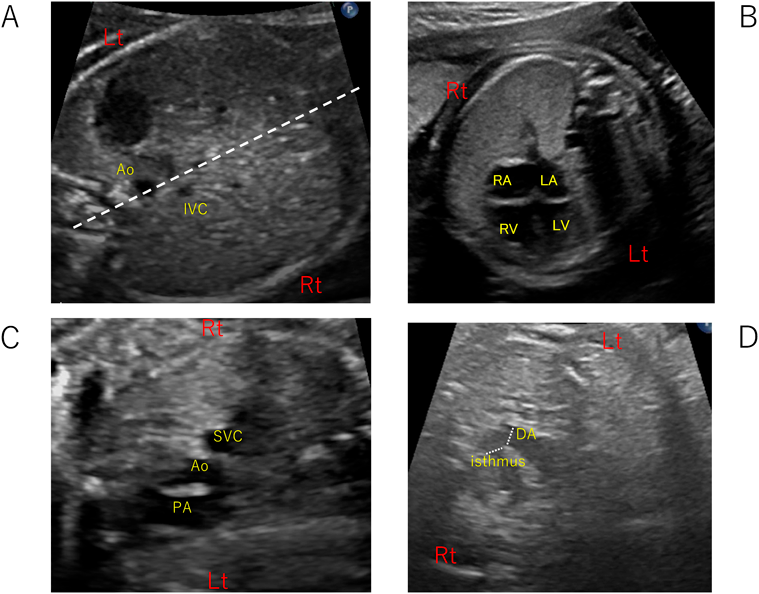

Abdominal view

腹部の横断面で確認すべきは腹部大動脈と下大静脈の位置と腹部臓器である(Fig. 2A).正常では,椎体の右側に下大静脈,左側に大動脈となる.ただし,実際には大動脈は椎体の真横ではなく斜め前と言った方が正確かもしれない.このviewはsitusの診断根拠となるため必ず確認しなければならない.左側相同では8割程度に下大静脈欠損を合併するが,その場合,奇静脈もしくは半奇静脈が上大静脈へ結合する.右側相同では,9割で腹部大動脈と下大静脈が(椎体から見て)同側に位置する.腹部臓器に関しては,胃と肝臓の位置確認が主となる.ちなみに,右側相同や左側相同の診断は,厳密には気管支分岐・心耳形態・腹部臓器の位置を全て確認する必要があるため,胎児心エコーだけでは正確な判断が困難な例も多く,胎児MRIなどの他のmodalityが必要になる.

Pediatric Cardiology and Cardiac Surgery 37(4): 265-276 (2021)

Fig. 2 Basic views

A: abdominal view. Note the location of IVC on the right side and Ao on the left side. The dotted line shows the central line of the abdomen. B: 4-chamber view. In a perfect transverse plane, a complete fetal rib is imaged. C: 3-vessel view. PA, Ao, and SVC are in a straight line. D: 3-vessel-trachea view. The isthmus and ductus are measured. Ao, aorta; DA, ductus arteriosus; IVC, inferior vena cava; LA, left atrium; LV, left ventricle; PA, pulmonary artery; RA, right atrium; RV, right ventricle; SVC, superior vena cava.

4-chamber view

4-chamber viewは胎児心エコーの基本中の基本であり,最重要ポイントである(Fig. 2B).正常心を検査する際に,常に適切な4-chamber viewを描出するよう心掛けることで,異常な4-chamber viewに気づきやすくなる.

3-vessel viewと3-vessel-trachea view

4-chamber viewの位置からプローベを胎児頭側に平行移動させると3-vessel viewが描出される(Fig. 2C).正常心では,左側から肺動脈–大動脈–上大静脈の順に並び,血管径もこの順序に小さくなる.4-chamber viewが描出できていれば,3-vessel viewは比較的簡単に描出できる.